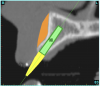

Using the interactive treatment-planning software application, the scan data was assimilated and both potential lateral incisor implant receptor sites were evaluated. It is a combination of the data and the methodology used to interpret the data that is the basis for defining a new paradigm in diagnosis and treatment planning. Proper evaluation of these images and correct use of the interactive treatment-planning software tools is essential in creating a decision tree of treatment options. First, the data from the scan was reformatted into panoramic, axial, and cross-sectional images. The undistorted cross-sectional images revealed the residual alveolar bone in the area of the right lateral incisor. Then, a simulated schematic implant was placed within the bone with an abutment extension to help visualize the connection to the restorative position of the tooth (Figure 4A). The Triangle of Bone® (TOB), a concept developed by the author to analyze bone quality, quantity, and disposition at prospective dental implant sites using CBCT scans, aided in determining available bone volume by defining a “zone” for proper implant placement18,19 (Figure 4B).

After reviewing the CT data and the decision tree, the bone within the “zone” of the TOB was evaluated and found to be satisfactory for implant placement. Because the goal of implant dentistry is not the implant but the tooth that is placed, true restorative-driven implant dentistry must begin with the assumption that the implant position should remain consistent with the tooth it is replacing, and the final implant-supported restoration.12,22-26 The TOB aids the clinician in understanding the link between the implant position and the desired restorative goal. The base of the geometric shaped “zone” is visualized by starting at the widest area of alveolar bone facially and superiorly. The apex of the triangle is positioned to bisect the alveolar crest (Figure 4B). The TOB, the overlay in the cross-sectional image, reveals whether adequate bone is available for implant placement. It also helps to identify concave facial bone defects, and accurately determine the width of bone at the crest. The author recommends using an interactive software application that provides the necessary measurement tools to accurately assess the bone anatomy.

Figure 4a  CT scan data was input into the treatment-planning software, which allowed (A) placement of a simulated implant and (B) the determination of the “zone” for proper placement.

Figure 4a

Figure 4b  CT scan data was input into the treatment-planning software, which allowed (A) placement of a simulated implant and (B) the determination of the “zone” for proper placement.

Figure 4b